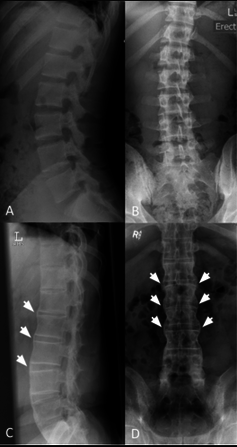

L’esempio più grave di SPA nei pazienti è la colonna vertebrale a canna di bambù, ossia la fusione delle vertebre che ne riduce la possibilità di movimento. I pazienti che soffrono di spondilite anchilosante non grave, come il caso estremo descritto in precedenza, soffrono comunque moltissimo e l’impatto sulle attività di tutti i giorni e sui lavori di routine può essere molto alto.

La spondilite anchilosante è una malattia infiammatoria che può causare la fusione delle vertebre della spina dorsale. Questa fusione rende la colonna vertebrale meno flessibile ed è responsabile della postura ingobbita. Se insorge anche nelle costole, può complicare la respirazione. Tale patologia è inserita nel gruppo delle Malattie Reumatiche Infiammatorie Croniche e Autoimmuni.

Nello specifico, la malattia insorge a causa di un’infiltrazione di macrofagi e altre sostanze del sistema immunitario nelle cartilagini, che provoca l’infiammazione delle articolazioni. Tale infiammazione, se non debitamente curata, dà origine al tessuto cicatriziale, formando dei ponti ossei tra le articolazioni e impedendo così il movimento delle vertebre.